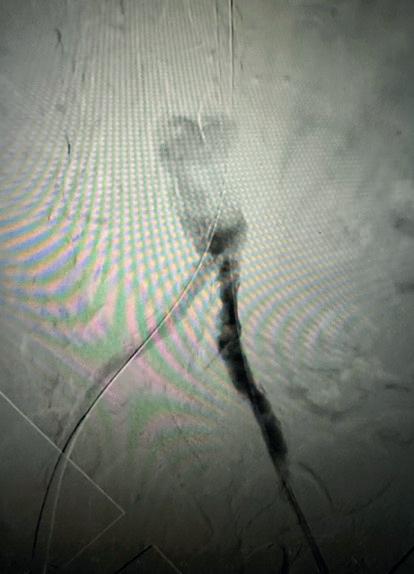

For those that qualify for intervention based on currently used criteria, vascular access is obtained in the standard fashion with ultrasound guidance. Caval venography is performed to ensure no anatomic abnormality, thrombosis or clot in transit. The right heart is then catheterised—I am a fan of the angled pigtail more so than a balloon-tipped catheter such as the Swan-Ganz as I feel its shape mirrors the anticipated trajectory. For each one of my PE interventions, a full right heart catheterisation is performed. A comfort with waveform analysis traversing right atrium, right ventricle and into the main pulmonary artery is paramount. These are standard displays in a cardiac catheterisation laboratory although not usual in the operating suite, so depending on your site of care, it is